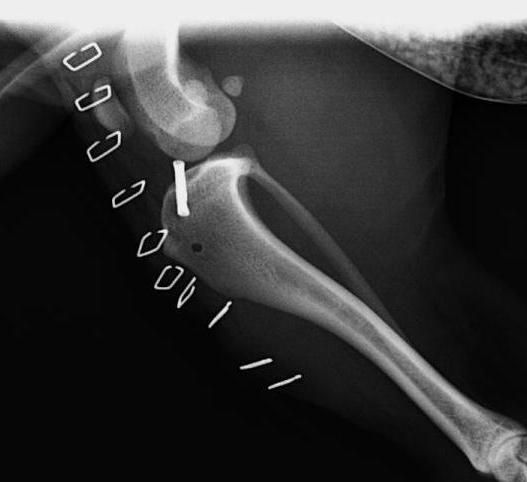

Artrodesis

Es una cirugía que consiste en fusionar articulaciones que tienen problemas de inestabilidad, dolor o artrosis, para eliminar el dolor y tener una buena funcionalidad y calidad de vida.

Se colocan placas especiales con tornillos, que adaptados a la forma que queremos que la articulación adopte una vez fusionada.